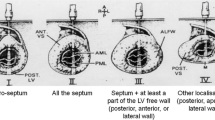

Demographics of the patients with HCM, H-LVH, and the control subjects are detailed in Table 1. There were no statistically significant differences between the H-LVH and HCM with regard to age, gender, body surface area across groups. No differences in LV ejection fraction, left atrial size or RV thickness was observed between groups, although the end-diastolic diameter was significantly increased in controls compared to HCM and H-LVH patients (<0.05 for both). None of the patients had evidence or right ventricular cavitary or left ventricular outflow obstruction at rest (defined as a resting late peaking LVOT gradient ≥30 mm Hg). Most frequently involved territories exhibiting prominent LVH in HCM patients were septal (81.2 %), followed by apical (15 %) and concentric LVH (3.8 %).